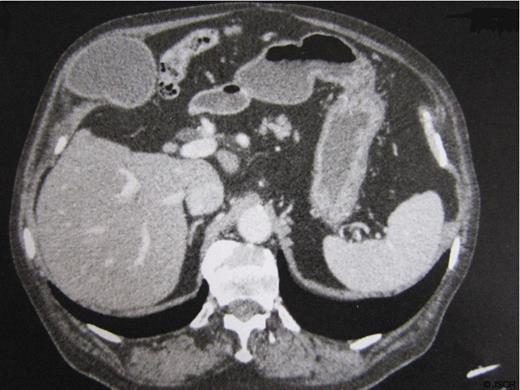

The patient was an 85 year-old man with history of hypertension, previous surgery for perforated diverticular disease (Hartmann procedure followed by reversal of colostomy). He had suffered from occasional pain in the right upper quadrant for several months. The physical examination showed a 5 cm mass in the right upper quadrant tender to palpation. Ultrasound and CT confirmed the presence of a lithiasic gallbladder herniated through the abdominal wall (fig.1), with a dilatation of the common bile duct that measured 11 mm, due to a 17 mm obstructive infundibular stone as it happens in Mirizzi syndrome type I (fig.2).